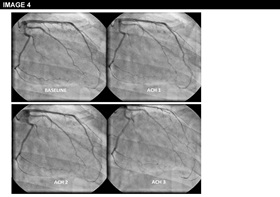

Physical examination is unremarkable. The resting ECG is normal with no ischaemic features (Image 1). She was referred for an ECG exercise stress test. She exercised for 6 min 35 seconds (Bruce protocol), achieved 131% of her heart rate and developed chest pain and breathlessness at peak exercise. Ischemic ST changes were noted which resolved slowly during recovery (Image 2). The patient was referred for cardiac catheterization which showed smooth unobstructed coronary arteries (Image 3). Provocation testing with acetylcholine was performed during angiography when incremental doses of acetylcholine 2mcg, 40mcg, 100mcg were injected in the left coronary system. This resulted in the reproduction of her symptoms, ST depression on the ECG and >75% diffuse epicardial coronary artery spasm of the left coronary artery (Image 4). The diameter of the coronary arteries returned to baseline after intracoronary nitrate administration and both the chest pain and the ECG changes subsided rapidly. Given the diffuse involvement of the distal segments of the coronary artery during the acetylcholine infusion, suggesting the presence of microvascular dysfunction, the patient underwent cardiac magnetic resonance perfusion scanning. Following adenosine stress, which reproduced her usual symptoms, the patient developed subendocardial hypoperfusion of the basal-mid inferior wall & adjacent septum & lateral wall with a circumferential pattern suggestive of microvascular angina (Image 5). On late gadolinium enhancement imaging there was no fibrosis or infarct (Image 6).